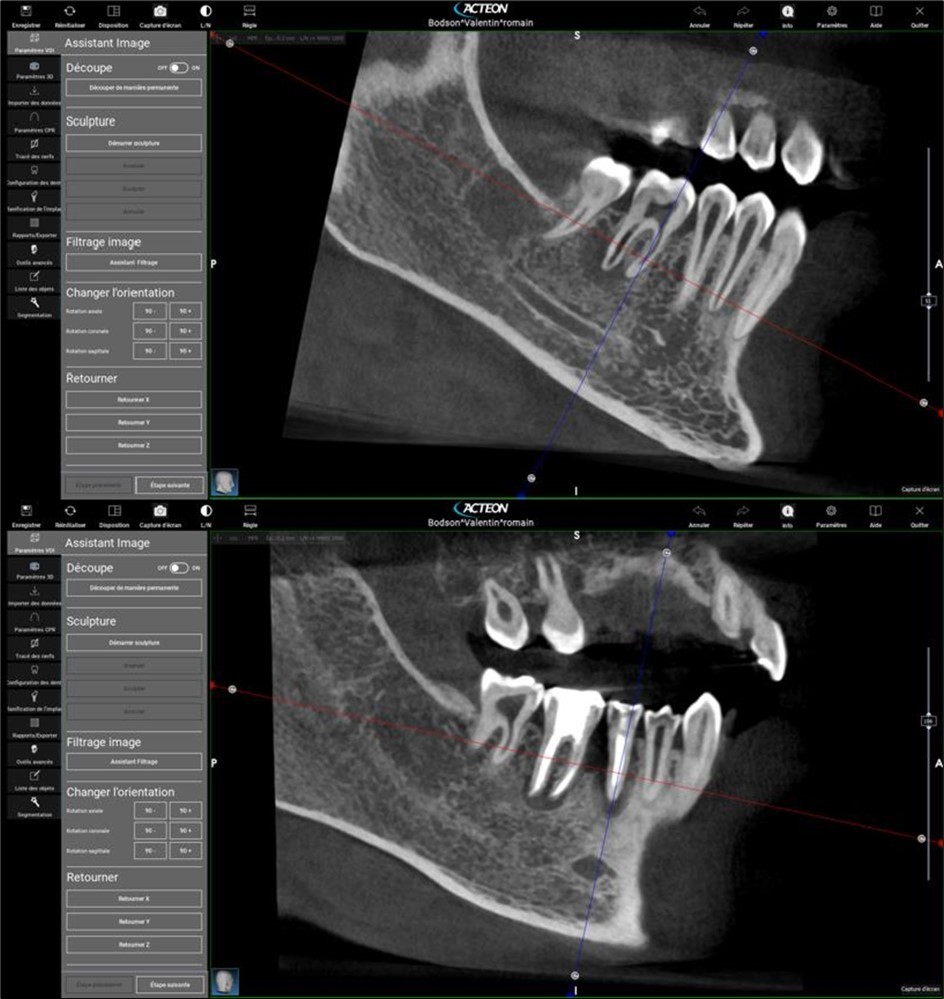

Periapical radiography (phosphorus number 2 plaque and X-MIND® Unity; Acteon) and cone-beam computed tomography (X-MIND® 3D; Acteon) (80 × 80, 150 Micron) were performed and showed periapical lesions on teeth 14, 15, 16, 24, 25, 26, 35, 36, and 46, as well as advanced endo-perio lesions on teeth 26 and 16. orthopantomogram (X-MIND® 3D; Acteon) and bitewings (phosphorus number 2 plaque and X-MIND® Unity; Acteon) also showed wide pulp chambers and roots canals. Figure 1, Figure 2

Figure 2.2. 3, 4, and 5 show periapical lesions on teeth 15, 16, 24, 25, 26, 35, 36, and 46.